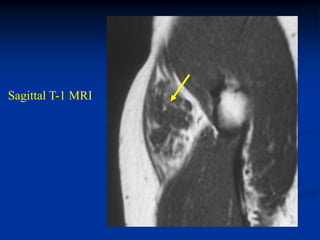

Case #1186

51 year male with

intramuscular lipoma

posterior compartment

thigh

Axial T-1 MRI

Case #1186 51 yearmale with intramuscular lipoma posterior compartment thigh

• 58.

• 59.